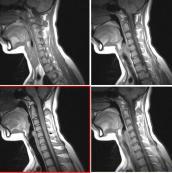

視神經(jīng)脊髓炎癥狀

• 視神經(jīng)脊髓炎

628健康網(wǎng)為您分享有關視神經(jīng)脊髓炎的癥狀,視神經(jīng)脊髓炎的治療方法,視神經(jīng)脊髓炎的預防知識,視神經(jīng)脊髓炎的癥狀圖片,視...